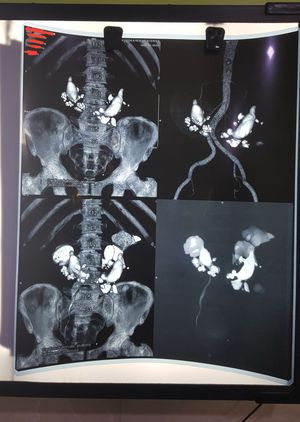

Multiple large renal pelvic and calyceal stones .

A 43 year old male after a minor road traffic accident presented to the hospital for the normal check up. On performing ultrasound incidental kidney stones were suspected. On performing CT scan multiple stones were confirmed.